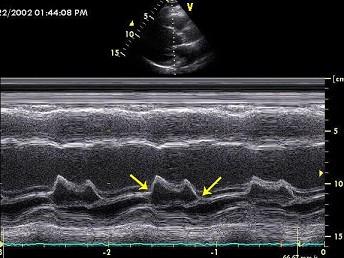

二尖瓣M型超声心动图,图中尖头所示两点称为?(?)A.E点和A点B.D点和C点C.F点和G点D.高点和底点E.前点和后点

问题 二尖瓣M型超声心动图,图中尖头所示两点称为?(?)

选项 A.E点和A点 B.D点和C点 C.F点和G点 D.高点和底点 E.前点和后点

答案 B